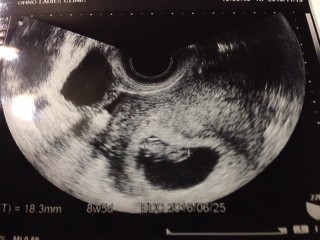

8w0dです。 前回は8w6dで稽留流産でした。 茶おりが出て心配で慌てて受診。 赤ちゃんの心拍は元気で大きさも標準と言われました! 茶おりの原因は子宮の入口に小さいポリープがあってそれが原因だろうと言うことでした。 今取ってしまうと流産や早産の可能性があるから、しばらく様子を見ましょうという事に。 とにかく赤ちゃんが元気で一安心でした。